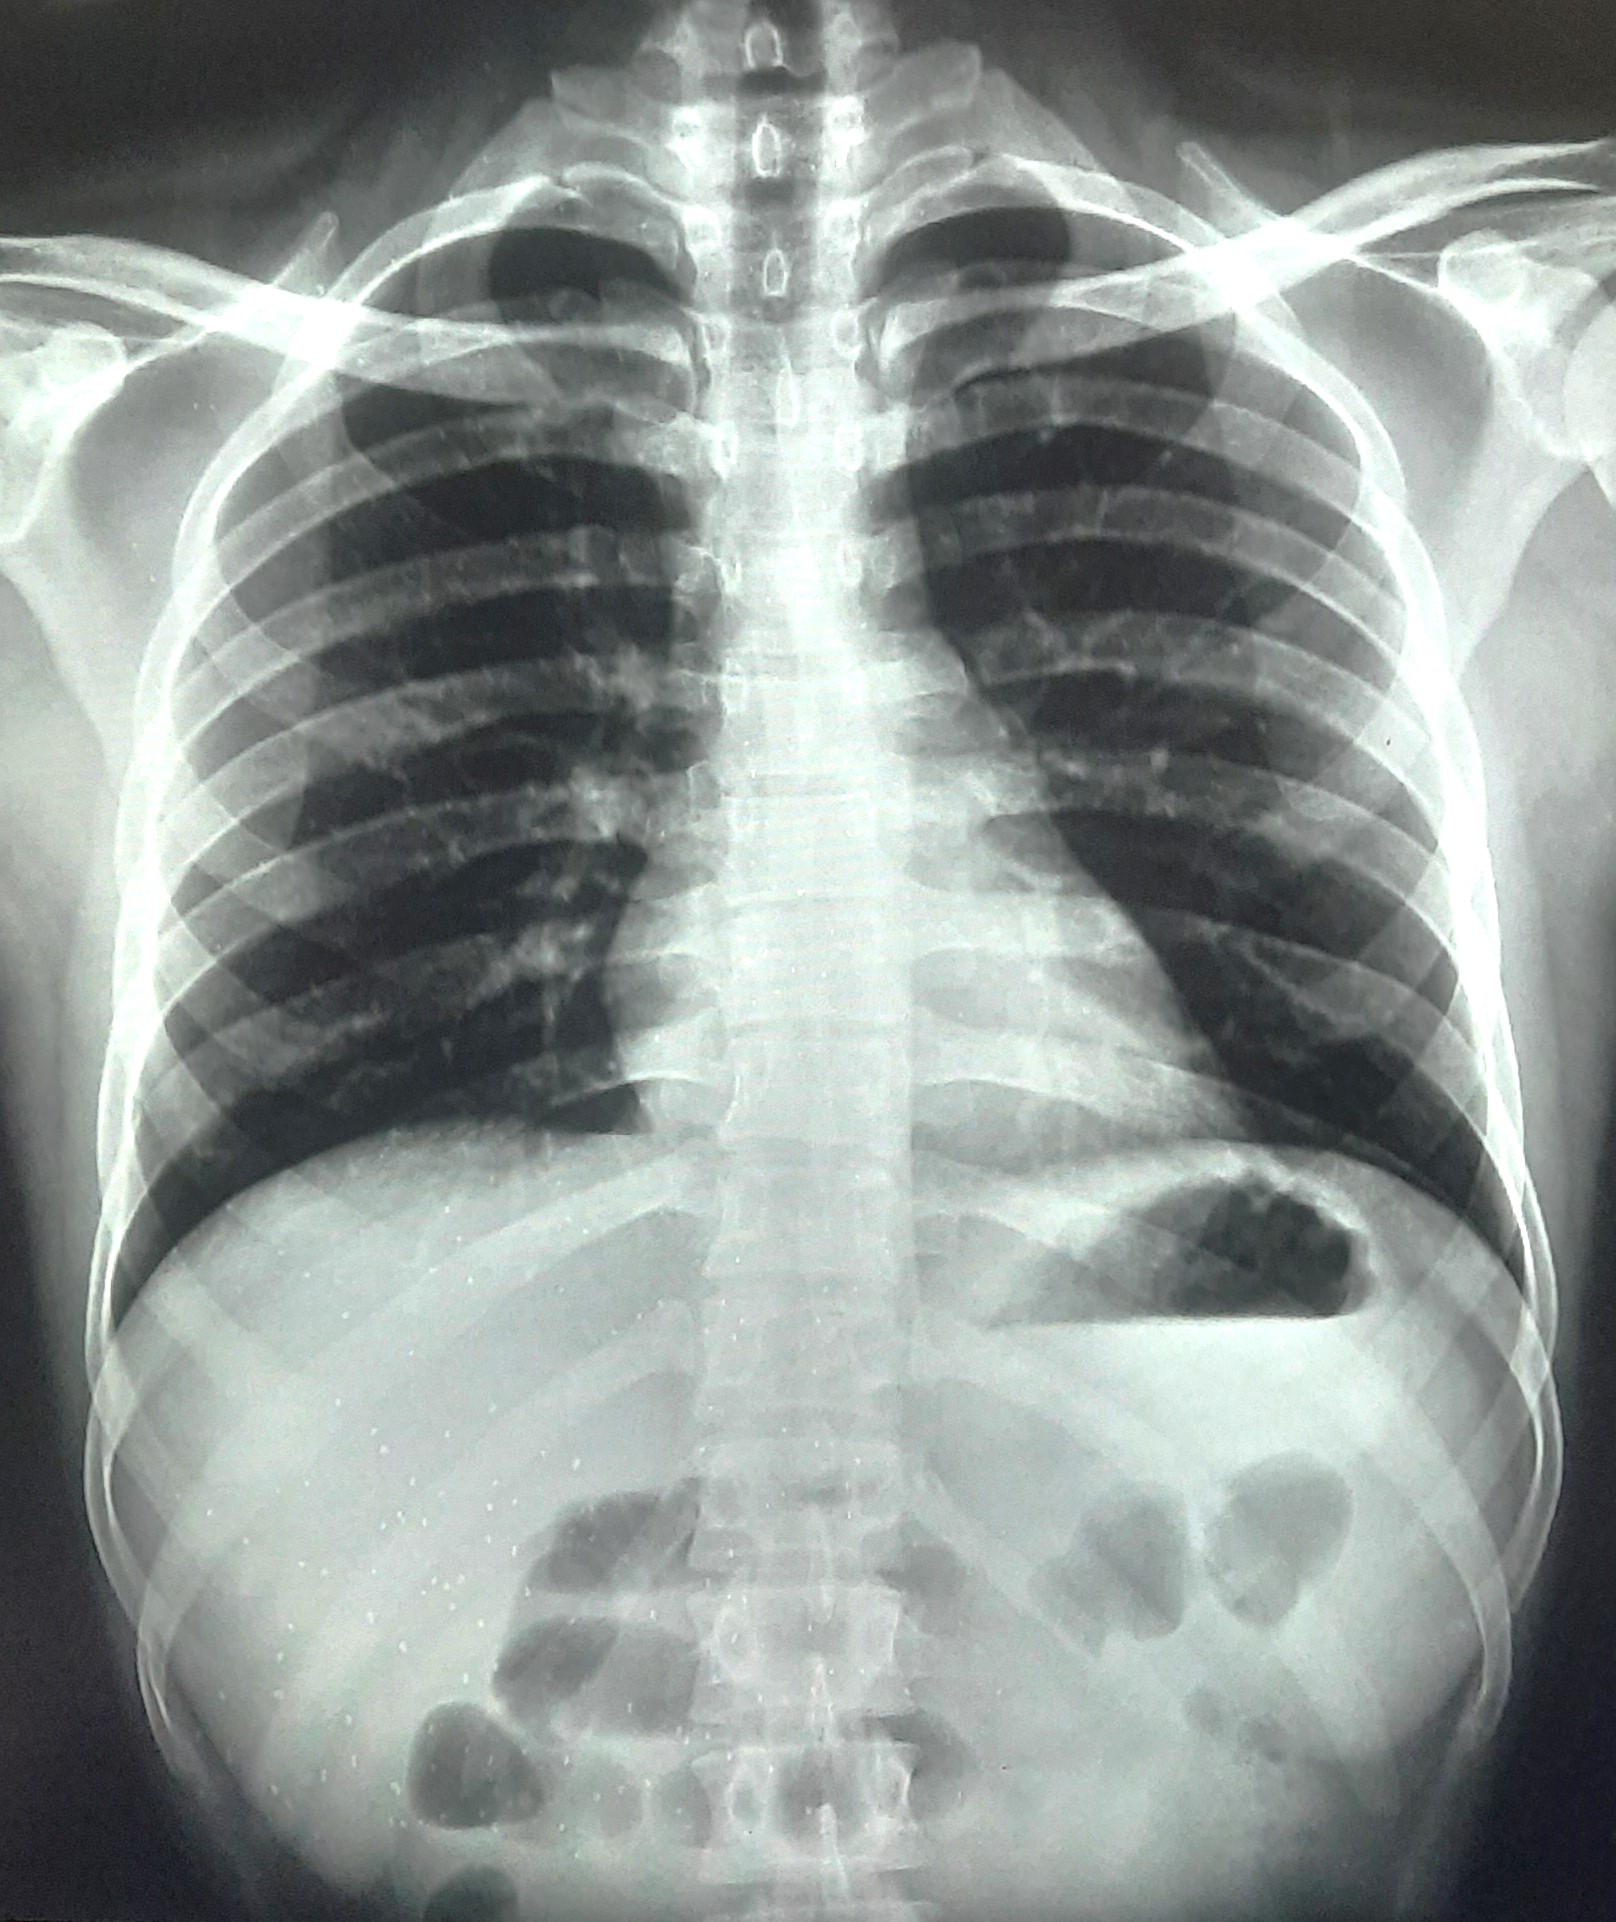

| 207 | IGGMC, Nagpur, Nagpur | P2 | 29-4265 | SHUBHAM MARATHE | Consent taken on Paper | 27 Yrs. |

Provisional Diag : LEFT SIDED CLINICALLY DIAGNOSED PLEURAL EFFUSION

Final Diag : LEFT SIDED CLINICALLY DIAGNOSED TUBERCULAR EMPYMA ON ATT FROM 9.11.2024 |

TB Case (Confirmed) | LEFT SIDED CP ANGLE BLUNTING | Abnormality visible on x-ray |